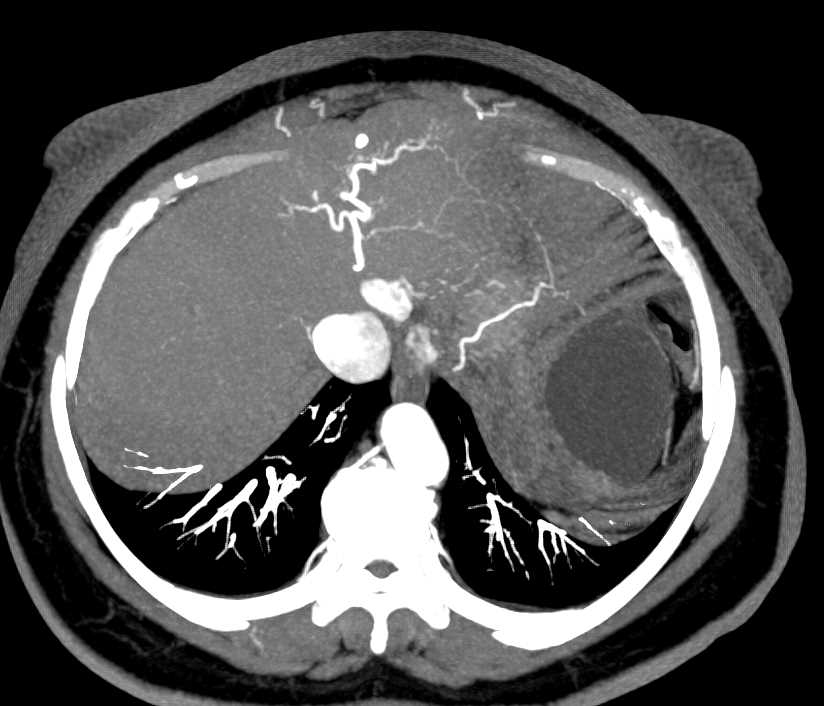

Healthy Liver, Ct Scan Photograph by Zephyr

Healthy Liver, Ct Scan Photograph by Zephyr

Fatty Liver Ct